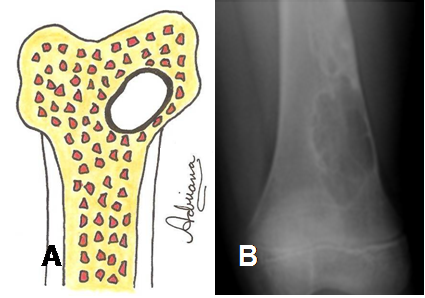

Fig 26. Lesión geográfica tipo 1A.

A: Diagrama de lesión bien definida y de bordes escleróticos.

B: Rx AP. Lesión excéntrica, bien definida y de bordes escleróticos, por defecto fibroso cortical.